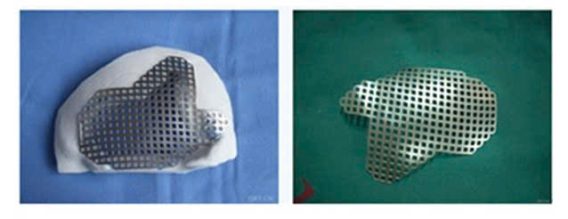

Được sử dụng để chế tạo tấm thép, ốc vít, khớp nối, và thậm chí cả xương nhân tạo, hợp kim titan hầu như không được cơ thể con người chấp nhận trong nhiều thập kỷ, điều này đã từng là vấn đề với các kim loại khác từ lâu, vậy tại sao hợp kim titan có thể xâm nhập vào cơ thể con người và cùng tồn tại một cách hòa bình? Khoa học đằng sau điều này sâu sắc hơn bạn nghĩ rất nhiều.

Hợp kim titan được sử dụng phổ biến nhất trong phẫu thuật gãy xương, ví dụ, gãy xương vụn cần phải dùng nẹp thép và vít để ghép các xương gãy lại với nhau, một ví dụ khác là hoại tử chỏm xương đùi ở người cao tuổi, cần thay khớp nhân tạo, trong đó hợp kim titan là vật liệu được ưu tiên, các dị tật bẩm sinh, vẹo cột sống và tái tạo sau khi cắt bỏ khối u xương cũng rất cần thiết.